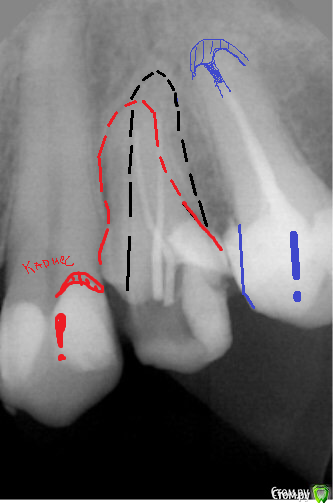

dr.Dre Опубликовано 13 апреля, 2016 Поделиться Опубликовано 13 апреля, 2016 Добрый день коллеги,24 зуб что скажете по снимку есть 3 канал?Два канала кальцинированы ввожу 10 к файл ничего,20 цепляет? Ссылка на комментарий

Ker Опубликовано 13 апреля, 2016 Поделиться Опубликовано 13 апреля, 2016 (изменено) Два там Изменено 13 апреля, 2016 пользователем Ker 2 Ссылка на комментарий